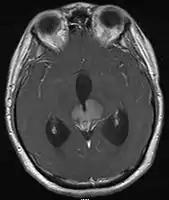

• Mainly located in midline structures, suprasellar region or pineal gland, also basal ganglia and hypothalamus

• Natural spread believed to be along subependymal lining of 3rd and 4th ventricles, leading to intraventricular relapse before spinal dissemination

Location